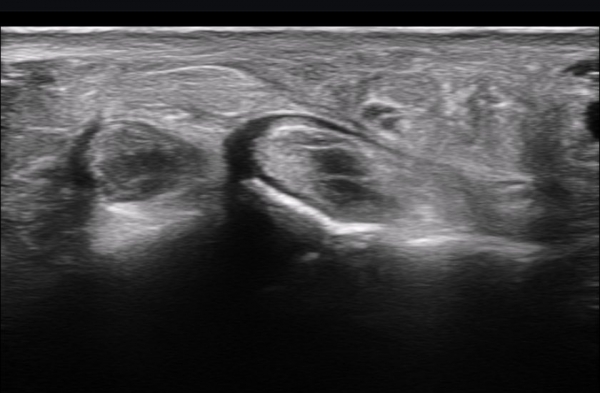

ºñº¹½Å°æ Á¾´Ü¸é°Ë»ç(»çÁø 14, 15)¿¡¼­ ºñº¹½Å°æÀÇ Àü¹ÝÀûÀÎ Àú¿¡ÄÚ ºÎÁ¾°ú ºñº¹½Å°æ ½ÉÃþÀ¸·Î ´Üºñ°ñ°Ç³»

³¶Á¾¼º º¯º¯ÀÌ °üÂûµÈ´Ù.